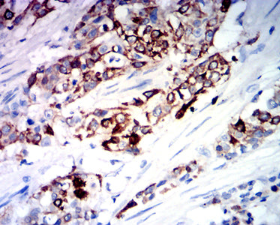

IHC    1/200 - 1/1000